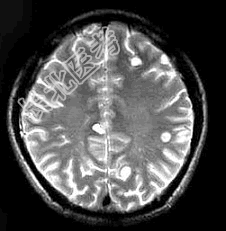

- 单项选择题患者,男, 29岁。头痛不适半个月。MRI扫描如图示。据此可作出下列最可能的诊断是 ( )

A、脑囊虫病

B、脑弓形虫病

C、脑结核

D、脑转移瘤